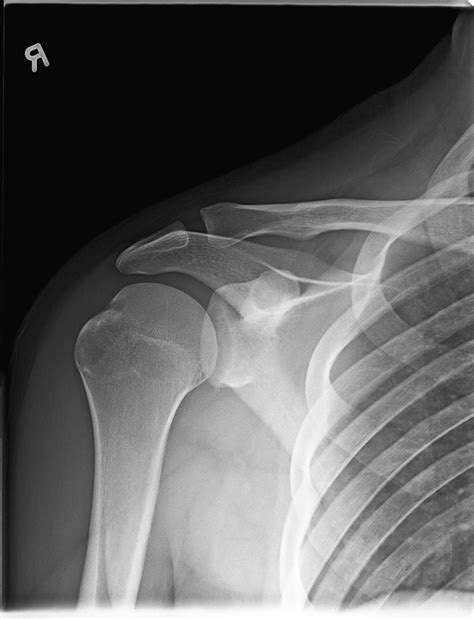

Interpreting a Shoulder Xray Normal

When a radiologist reviews a shoulder X-ray, they look for specific features that indicate a normal shoulder joint. These features include:

• Alignment of Bones: The humeral head should be properly aligned with the glenoid fossa of the scapula.

• Bone Density: The bones should have a uniform density without any areas of increased or decreased density.

• Joint Spaces: The joint spaces should be uniform and without any narrowing or irregularities.

• Soft Tissues: The soft tissues around the joint should appear normal without any swelling or abnormalities.

If all these features are present, the X-ray is considered Shoulder Xray Normal.

Common Findings in a Shoulder Xray Normal

A normal shoulder X-ray typically reveals the following:

• Humeral Head: The head of the humerus should be round and well-defined, sitting snugly in the glenoid fossa.

• Glenoid Fossa: The glenoid fossa should be smooth and without any erosions or irregularities.

• Acromioclavicular Joint: This joint should be well-aligned and without any signs of separation or dislocation.

• Clavicle: The clavicle should be intact and without any fractures or deformities.

• Soft Tissues: The soft tissues around the shoulder should appear normal, with no signs of swelling or inflammation.